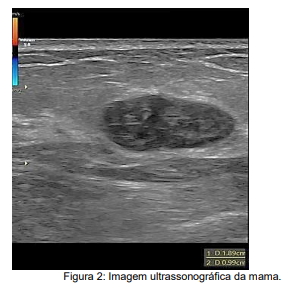

M.P.M., 22 anos, busca atendimento ginecológico ambulatorial assintomática mas muito chorosa e ansiosa, uma vez que sua sogra está em tratamento quimioterápico para câncer de mama e realizou ultrassonografia das mamas com achado ilustrado em Figura 2. Em relação ao diagnóstico mais provável e conduta, assinale a alternativa correta.